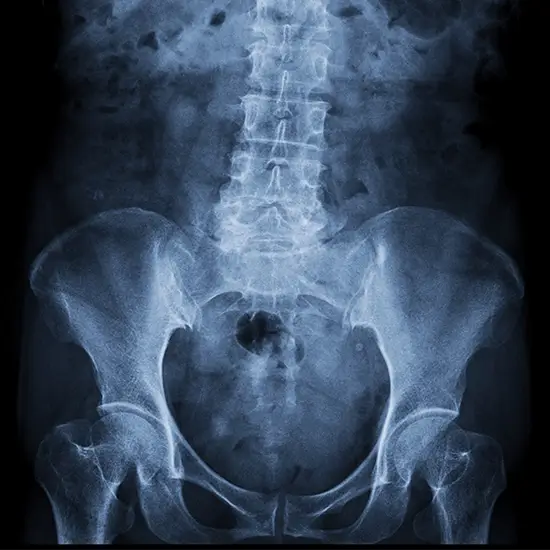

The hip joint facilitates movement and supports body weight. The X-ray of the Right Hip Joint reveals any hip fractures, dislocations, bone lesions, or degenerative illnesses. There is discomfort in the groin, the side of the hip, the buttocks, and the knee.

• To identify any fractures of the bones that comprise the hip joint and to monitor the bone's healing once it has been set.

• To identify infections, osteoporosis, malformations, and irregular bone development.

• To identify any osteoarthritis or dislocation of the hip joint that is suspected.